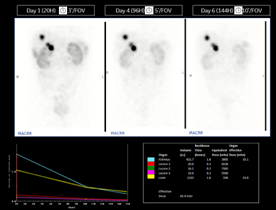

■270keVまで対応の検出器で177Luを確実に捉え、Theranosticsをサポート

がんの治療における放射性医薬品内用療法には177Luが用いられることがありますが、その投与量が多いことで従来のSPECT/CT装置では数え落としが発生し、中エネルギー帯であることから半導体であっても208keVのエネルギーを収集することが難しいとされてきました。StarGuideは270keVまでのエネルギーに対応することで、従来のSPECT/CT装置よりも数え落としを圧倒的に少なくし、コリメータを交換せずに177Luにおける113keV, 208keVの双方のエネルギーを収集することが可能になりました。画質、定量精度を向上させることで、Theranosticsにおける予後予測、治療における正常臓器への影響をより正確に導き出すサポートを行います。

※上記図:270keVまで対応の検出器でTheranosticsをサポート